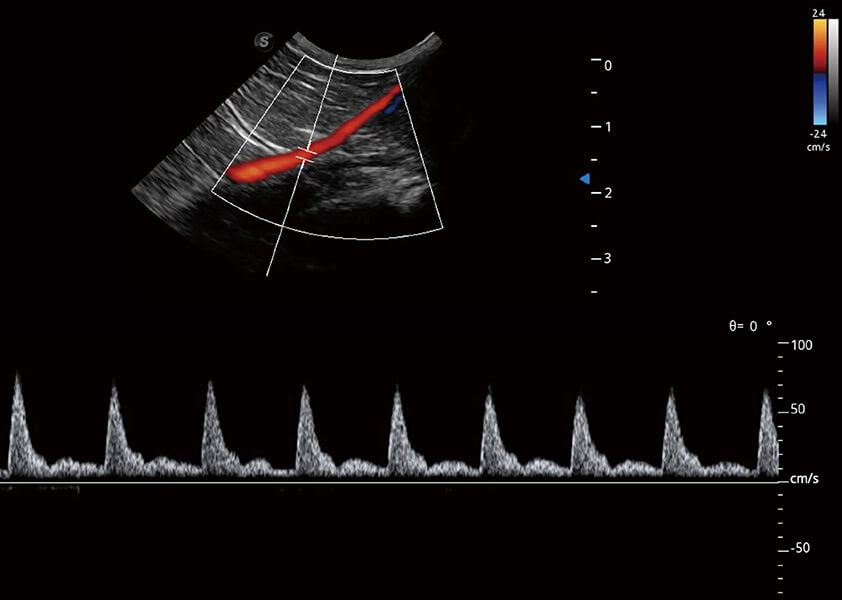

ProPet 60 作為一款高端臺(tái)式動(dòng)物超聲設(shè)備,為動(dòng)物醫(yī)生的日常診斷提供了一系列貼合動(dòng)物臨床需求、解決臨床實(shí)際問(wèn)題的高級(jí)成像功能。憑借全系列高清探頭,滿(mǎn)足醫(yī)生對(duì)腹部、心臟、生殖、淺表、肌骨等成像的所有需求,切實(shí)幫助您提升檢查效率,提高診斷信心。